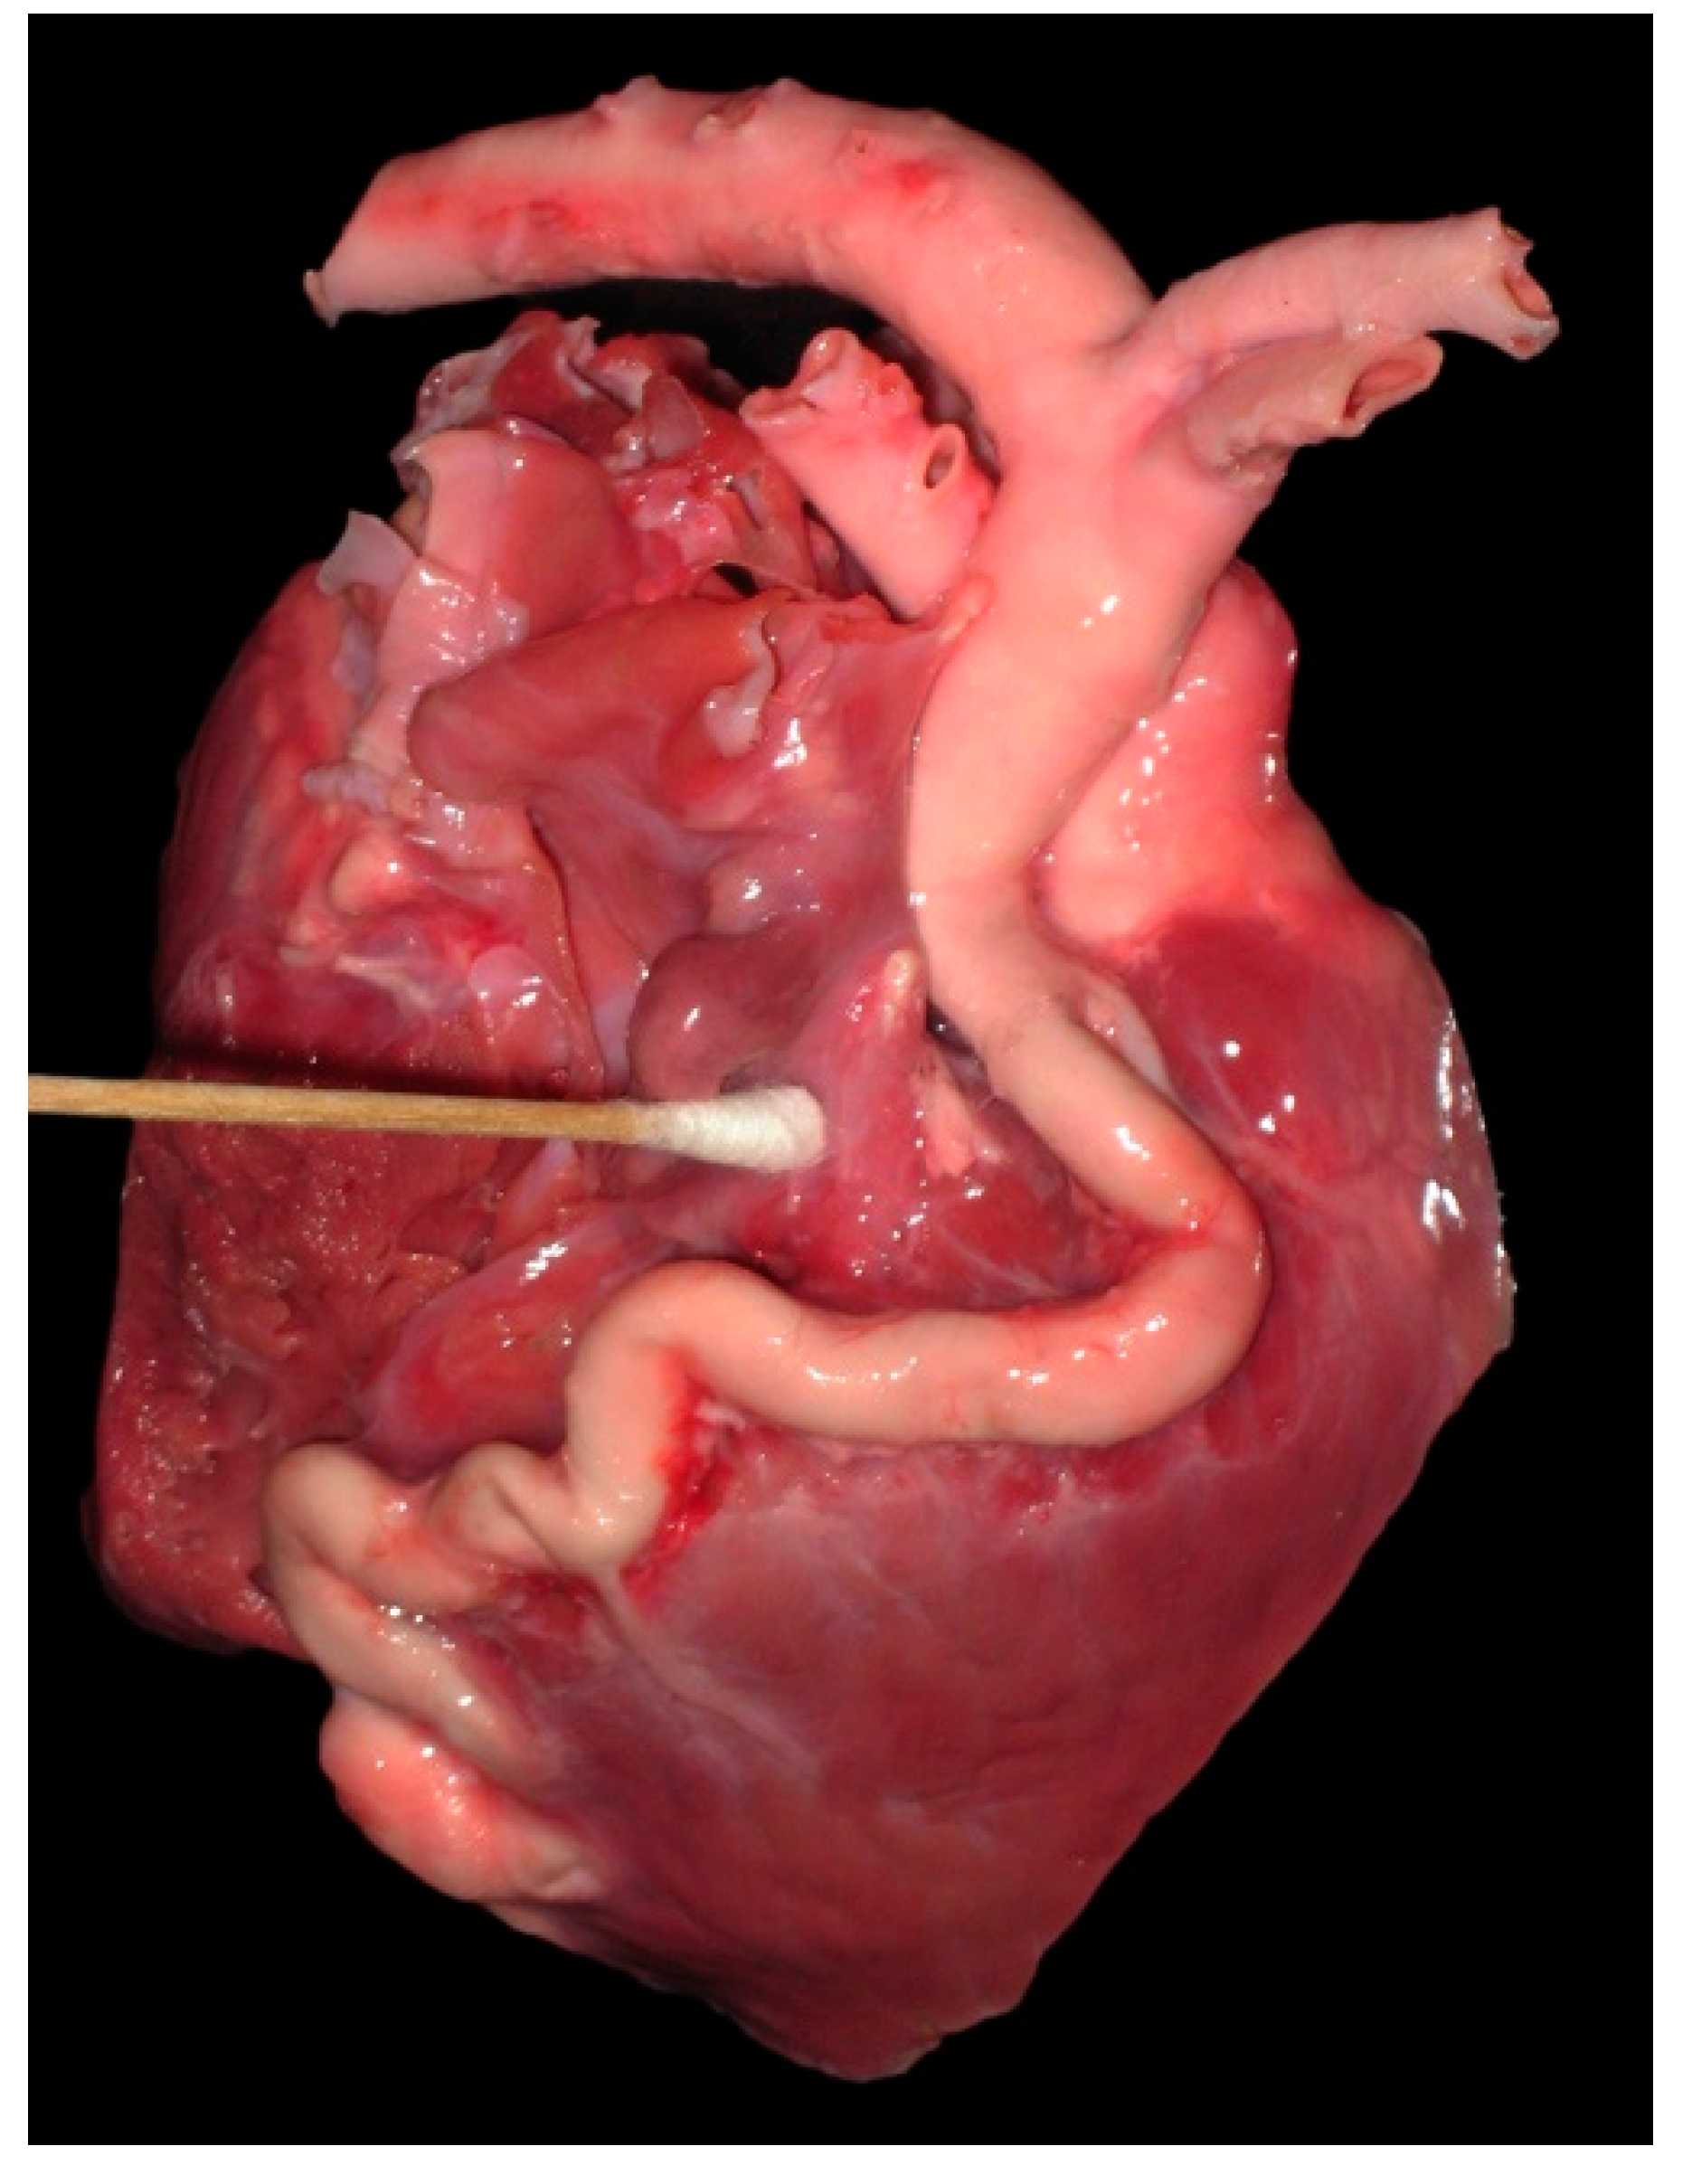

Figure 9.

Photograph of the heart from a 6-day-old llama cria showing a severely dilated and tortuous right coronary artery fistula, which drained to the proximal right ventricle.